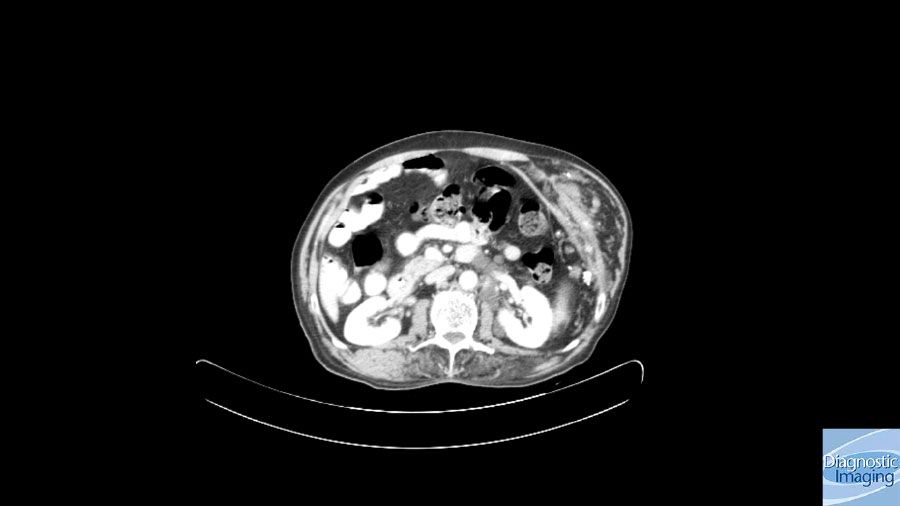

Case History: 65-year-old with lower left chest wall swelling since childhood.

Case History: 65-year-old patient presented with lower left chest wall swelling since childhood.